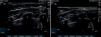

Results and conclusionsThe ultrasound sequence to perform this block is shown, together with simple X-ray dye images and gadolinium MRI images to understand the spread and pathways that can explain the benefit of this novel approach.

Resultados y conclusionesMostraremos la secuencia ecográfica para poder realizar este bloqueo junto con imágenes con contraste radiográfico y resonancia magnética con gadolinium para poder entender los beneficios de este bloqueo.